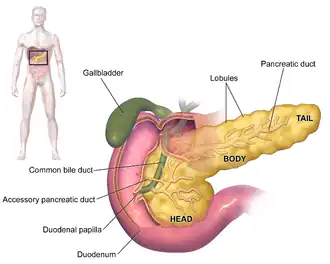

Anatomy of the human pancreas | |

The pancreas is an organ that in humans lies in the abdomen, stretching from behind the stomach to the left upper abdomen near the spleen. In adults, it is about 12–15 centimetres (4.7–5.9 in) long, lobulated, and salmon-coloured in appearance.[7]

Anatomically, the pancreas is divided into a head, neck, body, and tail. The pancreas stretches from the inner curvature of the duodenum, where the head surrounds two blood vessels: the superior mesenteric artery and vein. The longest part of the pancreas, the body, stretches across behind the stomach, and the tail of the pancreas ends adjacent to the spleen.[7]

Two ducts, the main pancreatic duct and a smaller accessory pancreatic duct run through the body of the pancreas. The main pancreatic duct joins with the common bile duct forming a small ballooning called the ampulla of Vater (hepatopancreatic ampulla). This ampulla is surrounded by a muscle, the sphincter of Oddi. This ampulla opens into the descending part of the duodenum. The opening of the common bile duct into main pancreatic duct is controlled by sphincter of Boyden. The accessory pancreatic duct opens into duodenum with separate openings located above the opening of the main pancreatic duct.[7]

Parts

The head of the pancreas sits within the curvature of the duodenum, and wraps around the superior mesenteric artery and vein. To the right sits the descending part of the duodenum, and between these travel the superior and inferior pancreaticoduodenal arteries. Behind rest the inferior vena cava, and the common bile duct. In front sit the peritoneal membrane and the transverse colon.[7] A small uncinate process emerges from below the head, situated behind the superior mesenteric vein and sometimes artery.[7]

The neck of the pancreas separates the head of the pancreas, located in the curvature of the duodenum, from the body. The neck is about 2 cm (0.79 in) wide, and sits in front of where the portal vein is formed. The neck lies mostly behind the pylorus of the stomach, and is covered with peritoneum. The anterior superior pancreaticoduodenal artery travels in front of the neck of the pancreas.[7]

The body is the largest part of the pancreas, and mostly lies behind the stomach, tapering along its length. The peritoneum sits on top of the body of the pancreas, and the transverse colon in front of the peritoneum.[7] Behind the pancreas are several blood vessels, including the aorta, the splenic vein, and the left renal vein, as well as the beginning of the superior mesenteric artery.[7] Below the body of the pancreas sits some of the small intestine, specifically the last part of the duodenum and the jejunum to which it connects, as well as the suspensory ligament of the duodenum which falls between these two. In front of the pancreas sits the transverse colon.[8]

The pancreas narrows towards the tail, which sits near to the spleen.[7] It is usually between 1.3–3.5 cm (0.51–1.38 in) long, and sits between the layers of the ligament between the spleen and the left kidney. The splenic artery and vein, which also passes behind the body of the pancreas, pass behind the tail of the pancreas.[7]